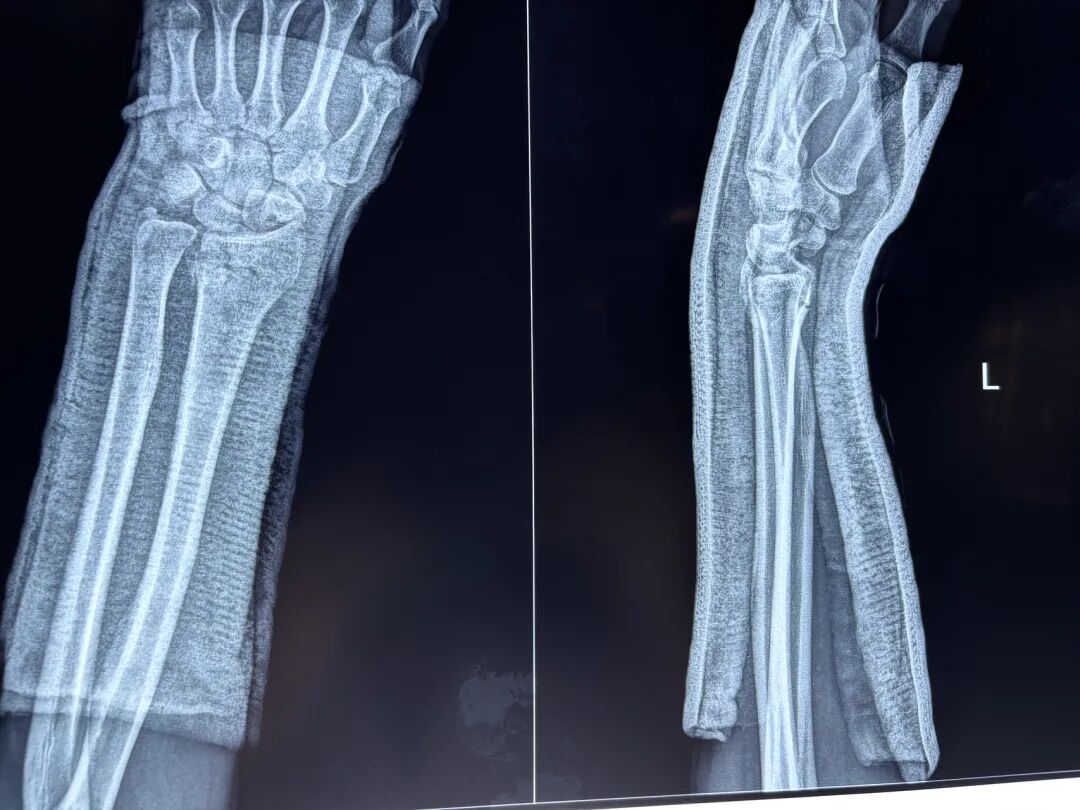

复查与注意事项:

1. 首次复查时间:复位后 3-7天(肿胀消退后)。 检查项目: X线片确认骨折对位情况(是否存在再移位)。 评估石膏松紧度(过紧可能压迫神经血管,过松易移位)。 观察手指颜色、温度、活动度(排查腕管综合征或血液循环障碍)。

3. 愈合期复查时间:复位后 6周(儿童可能缩短至4周,老年人或骨质疏松者延长)。 检查项目: X线评估骨痂形成情况,决定是否拆除外固定。 拆除石膏后检查腕关节活动度,必要时转康复科。

日常注意事项

1.固定护理保持石膏或支具干燥、清洁,避免负重或剧烈活动。 抬高患肢(高于心脏水平)减轻肿胀,尤其是复位后前48小时。 禁止自行拆除固定装置。

2.功能锻炼早期(复位后1-2周): 主动活动手指、肘关节和肩关节(预防僵硬和血栓)。 中期(4周左右): 在医生指导下尝试轻柔的腕关节屈伸(如无移位)。 后期(6周拆除固定后): 逐步进行腕关节力量训练(握力球、阻力带),避免暴力拉伸。